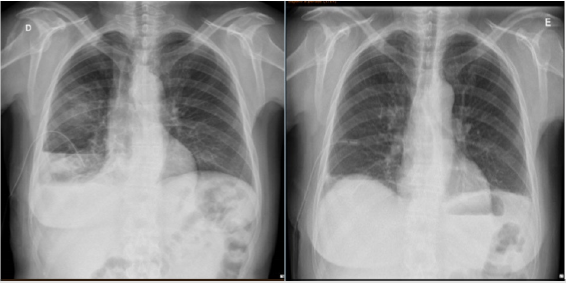

One week later, after maintaining pleural effusion even with a thoracic drain (drainage above 500mL day), she was submitted to Video-assisted thoracoscopic surgery (VATS) for pleural effusion drainage, pleural biopsy and pleurodesis (Figures 2 & 3). No suspicious implants were documented during VATS. The results showed no malignant cells and follow up thoracic x-rays revealed residual pleural effusion. She then underwent surgery with extemporaneous examination of the adnexal tumor. Histopathological findings were consistent with HGSOC and cytoreductive surgery was performed: left anexectomy, segmental resection of sigmoid and omentectomy. The pathology report documented a FIGO stage IIB with extrinsic infiltration of sigmoid onto muscularis propria. The tumor demonstrated solid and papillary patterns, and the classic slit-like spaces. The cells showed typical nuclear pleomorphism, prominent nucleoli, and numerous mitotic figures. Immunohistochemistry confirmed nuclear expression of WT1, strong diffuse p16 immunoreactivity and abnormal pattern of p53 expression (mutation-type labelling) represented by strong diffuse staining in > 80% of tumor cells. The histological and immunohistochemical findings were of a HGSOC (Figure 4). Ascitic citology was negative for malignant cells. Postoperative CA125 was 43.3U/mL, she had no clinical evidence of ascites or pleural effusion and started adjuvant chemotherapy with carboplatin/paclitaxel (Figure 5).

Figure 4: A-E. High-grade serous carcinoma. Epithelial neoplasm with solid and papillary patterns, and the classic slit-like spaces (A). The neoplastic cells show nuclear pleomorphism, prominent nucleoli, and mitotic figures (B). Immunohistochemistry confirmed WT1 (C), p16 (D) and p53 (E) positivity, the latter with a mutation-type labelling.